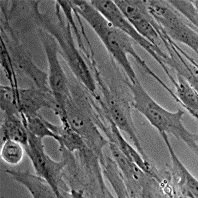

Морфология:

фибробластоподобная